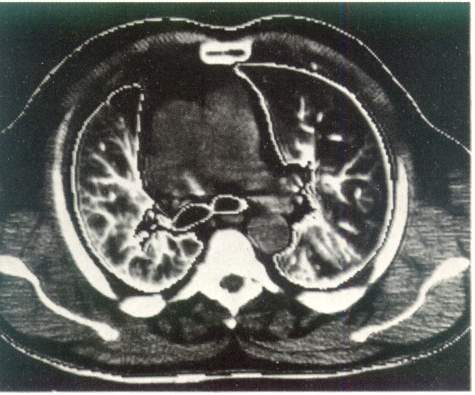

Рис. 3. Компьютерная томография органов грудной клетки.

Норма.

Компьютерная томография дает возможность получить наиболее полную

рентгенологическую информацию об опухолях и кистах средостения, сосудистых изменениях

в легких, аневризмах, о состоянии трахеобронхиального дерева,

характере и структуре «шаровидных образований в легких», патологических

изменениях в плевре, грудной стенке, особенно при ее злокачественных поражениях

(рис. 3).